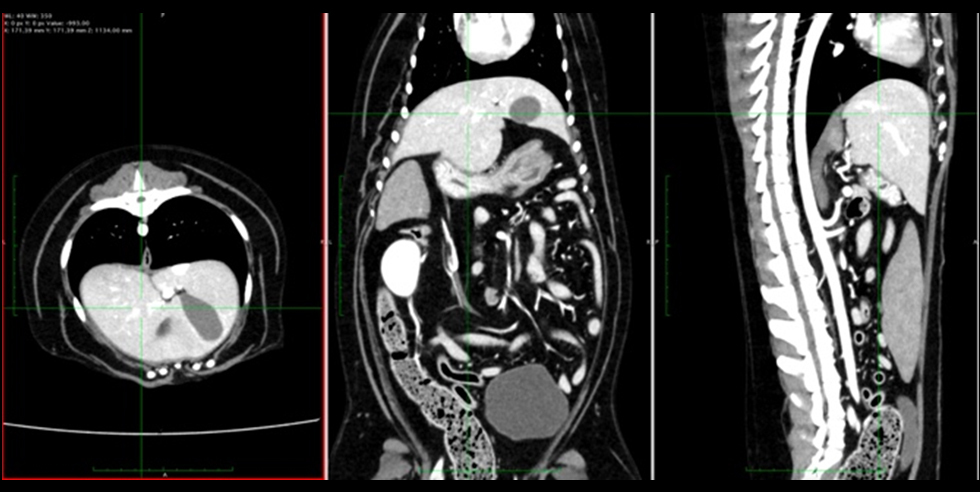

撮影法には二通りあり、造影剤を使用しない単純CTと造影剤を使用する造影CTがあります。また、時間を設定して繰り返し撮影する多層撮影などの特殊撮影を行うことで、さらにその精度が高まります。

造影剤を用いたCT画像は血管内や血流が豊富な組織が白く描出され、画像のコントラストが明瞭になります。単純CTで区別がつかない病変の発見や血管内・各臓器の血流状態がわかり、診断の上では欠かせない情報となります。腫瘍に関しては腫瘍の良悪性や進行度合いなどの鑑別も可能です。基本的には単純CTと併用して診断に用いられます。

症例①:組織球性肉腫

組織球性肉腫とは

極めて悪性度が高い腫瘍で、急速に全身へ播種(種をまいたようにバラバラと広がること)・転移します。好発部位は脾臓・肝臓・肺・骨髄・リンパ節とされていますが、あらゆる臓器で発生する可能性があります。

| 種類 | 犬 ビーグル |

|---|---|

| 年齢 | 8歳(当時) |

| 主訴 | 他院の紹介で腹部内にできものがあり、精密検査をご希望で来院 |

| 検査 | 全身の造影CT検査 |

その後は緩和治療を行い、経過をみました。